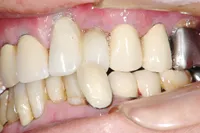

インプラントを使用した入れ歯の症例

■治療前

■治療後

| 主訴 | しっかりかみたい(咬合障害) |

| 治療方法 | 費用を抑える為、全てインプラントではなく、インプラントを土台とした入れ歯の治療 |

| 治療期間 | 約6か月 |

| 通院回数等 | 約20回 |

| 費用 | 約150万円 |

| リスク・副作用 | 術後の腫れ・痛み |